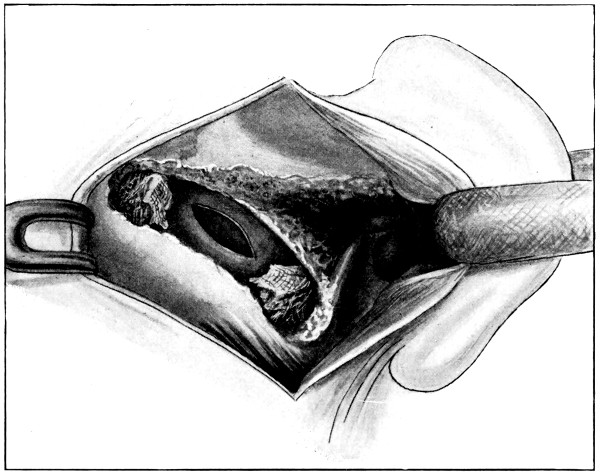

| 79. The exposure of a temporo-sphenoidal abscess | 265 |

| 80. The ‘radical’ mastoid operation (after Hunter Tod) | 269 |

| 81. Exploration for a temporo-sphenoidal abscess (after Hunter Tod) | 270 |

| 82. Exploration for a cerebellar abscess (after Hunter Tod) | 271 |

| 86. A case of Hernia cerebri and the abscess after removal | 292 |